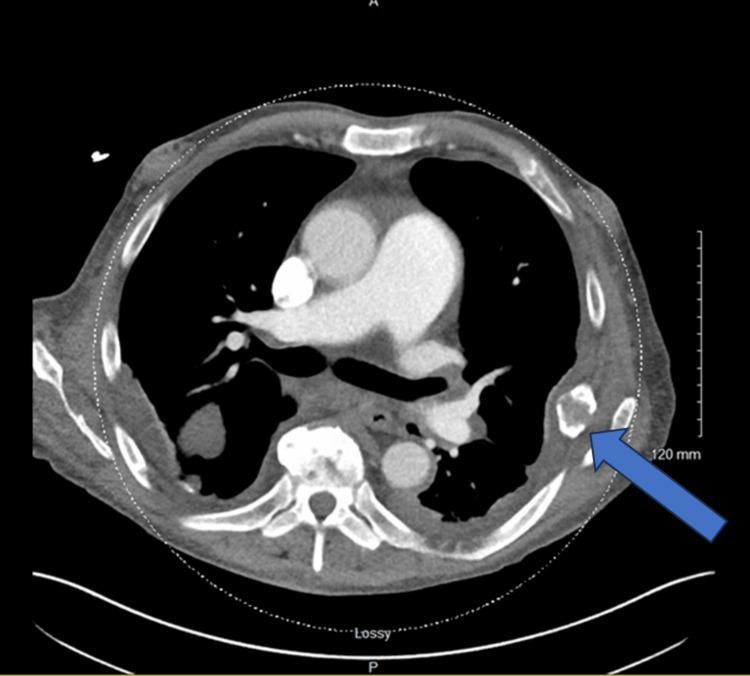

Brown tumors (also known as osteitis fibrosa cystica) are rare complications of end-stage renal disease (ESRD) and secondary hyperparathyroidism (HPT), characterized by focal bone lesions that resemble neoplasms. They are often misdiagnosed as metastatic bone disease, especially in patients with a history of malignancy. We present a case of a 60-year-old man with a history of renal cell carcinoma (RCC), and ESRD on hemodialysis (HD), who developed diffuse bone lesions on imaging with osteolytic/osteoblastic appearance concerning metastases, but on further workup was found to have brown tumors. We discuss the treatment and outcome and briefly review the relevant medical literature.

棕色瘤(也称为纤维囊性骨炎)是终末期肾病(ESRD)和继发性甲状旁腺功能亢进(HPT)的罕见并发症,其特征为类似肿瘤的局灶性骨病变。它们常被误诊为骨转移瘤,尤其是在有恶性肿瘤病史的患者中。我们报告一例60岁男性病例,该患者有肾细胞癌(RCC)病史,正在接受血液透析(HD)治疗的ESRD,影像学检查发现有弥漫性骨病变,呈溶骨/成骨表现,怀疑为转移瘤,但进一步检查发现是棕色瘤。我们讨论了治疗方法和结果,并简要回顾了相关医学文献。